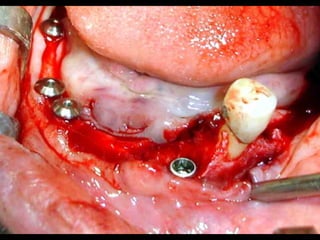

Plastia de maxilares para implantes dentales.

Plastia alveolar con factores de crecimiento y

traspalnate de hueso cadaverico

La conformación quirúrgica de un contorno alveolar adecuado es

determinante para la correcta aplicación y aceptación de los implantes

de titanio, aquí proponemos una técinica para lograr el espesor óseo

suficiente y la corrección estética del proceso, ya que antiguamente al

extraer un diente se acostumbraba presionar las tablas alveolares

“para cohibir la hemorragia”, con el colapso subsiguiente de la región.

La aplicación de implantes requiere de una cantidad y calidad de hueso

Importantes para sostener el metal en un área de estroma óseo

Saludable. Esto se logra efectuando una valoración adecuada de las

Características sistémicas del paciente y no injertando hueso o haciendo

Plastías indiscriminadamente.

He dado algunas directrices en el área de “consideraciones sobre

Implantes”

Este tipo de procedimientos puede considerarse como una forma de cirugía

preprotésica, la cual debe efectuarse con un conocimiento integral de las

alteraciones locales y sistémicas del paciente.

En mi práctica he observado el entusiasmo simplista de muchos odontólogos

practicando este tipo de intervenciones en pacientes con padecimientos que

afectan directamente al hueso (vejez, osteoporosis, diabetes, tumores óseos, etc.)

De ahí mi invitación a que estos procedimientos se efectúen apoyándose en

personas que hayan tenido un entrenamiento hospitalario a nivel de Residencia en

Cirugía Máxilofacial.